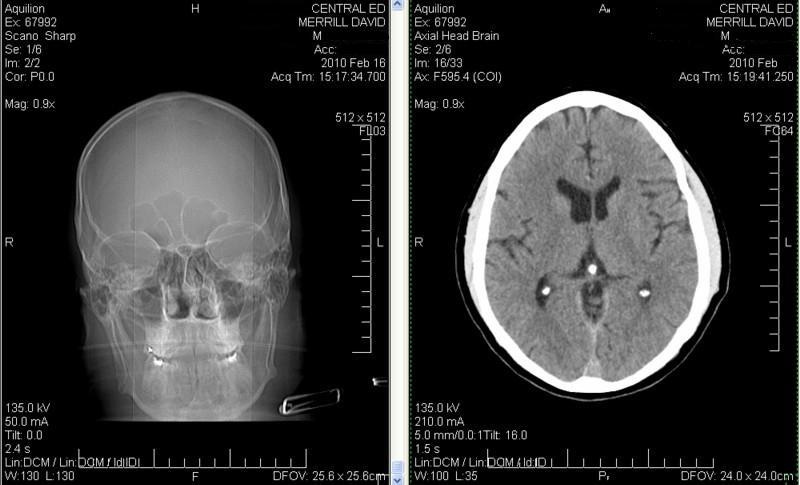

Hydroxyapatite Toothpaste? Mulberry-like Concretions on the Pineal Gland?

The “It (myeloconia is “brain dust”) consists of small crystals that are less than 20 microns in length and that are completely distinct from the often-observed mulberry-type hydroxyapatite concretions (calcification of the pineal gland)”. Mix the potassium or calcium hydroxyapatite (feldspar) she was (she has quit) putting on her gums and teeth with mica (biotite or muscovite) and quartzite and you produce a stone called granite. Oligoclase or plagioclase, depending on the potassium or calcium mentioned.

The sacking of Jerico may be examined because the hydroxyapatite composition and resonant frequency is the same, albeit I am not saying calcification of the pineal gland is granite - but that it is calcite in a different crystalline configuration. No communication with the mulberry like concretions: